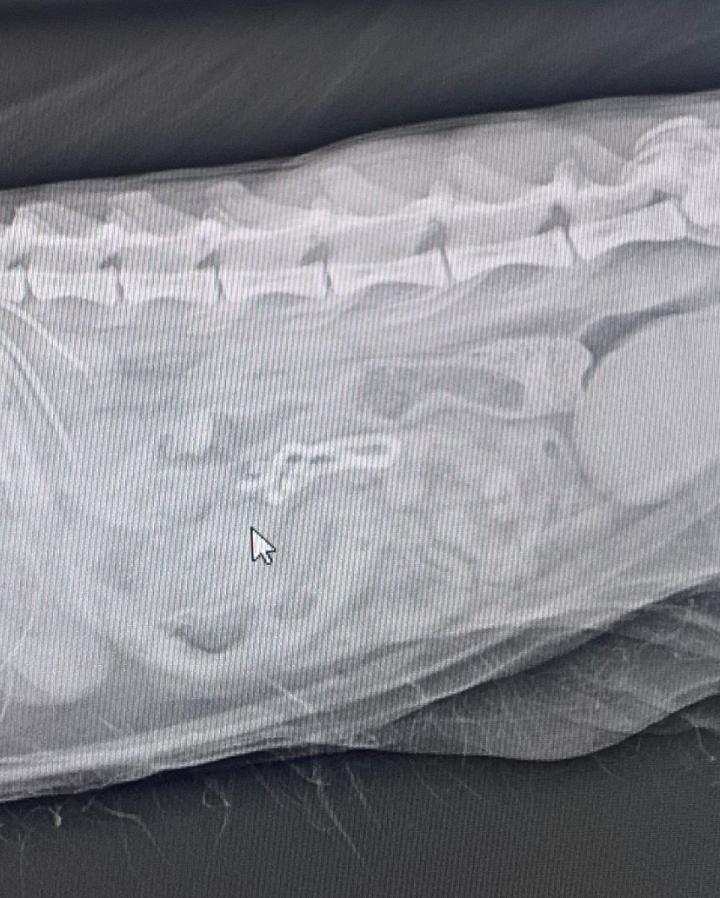

何も食べてない割に胃が張ってるね。これは誤飲かなぁ…とレントゲン撮影。バッチリ長細い何かが腸に写ってます😨

腸を動かし便で出てくれればいいけど…と点滴開始。一向に出てくる気配なし。入院となりました。